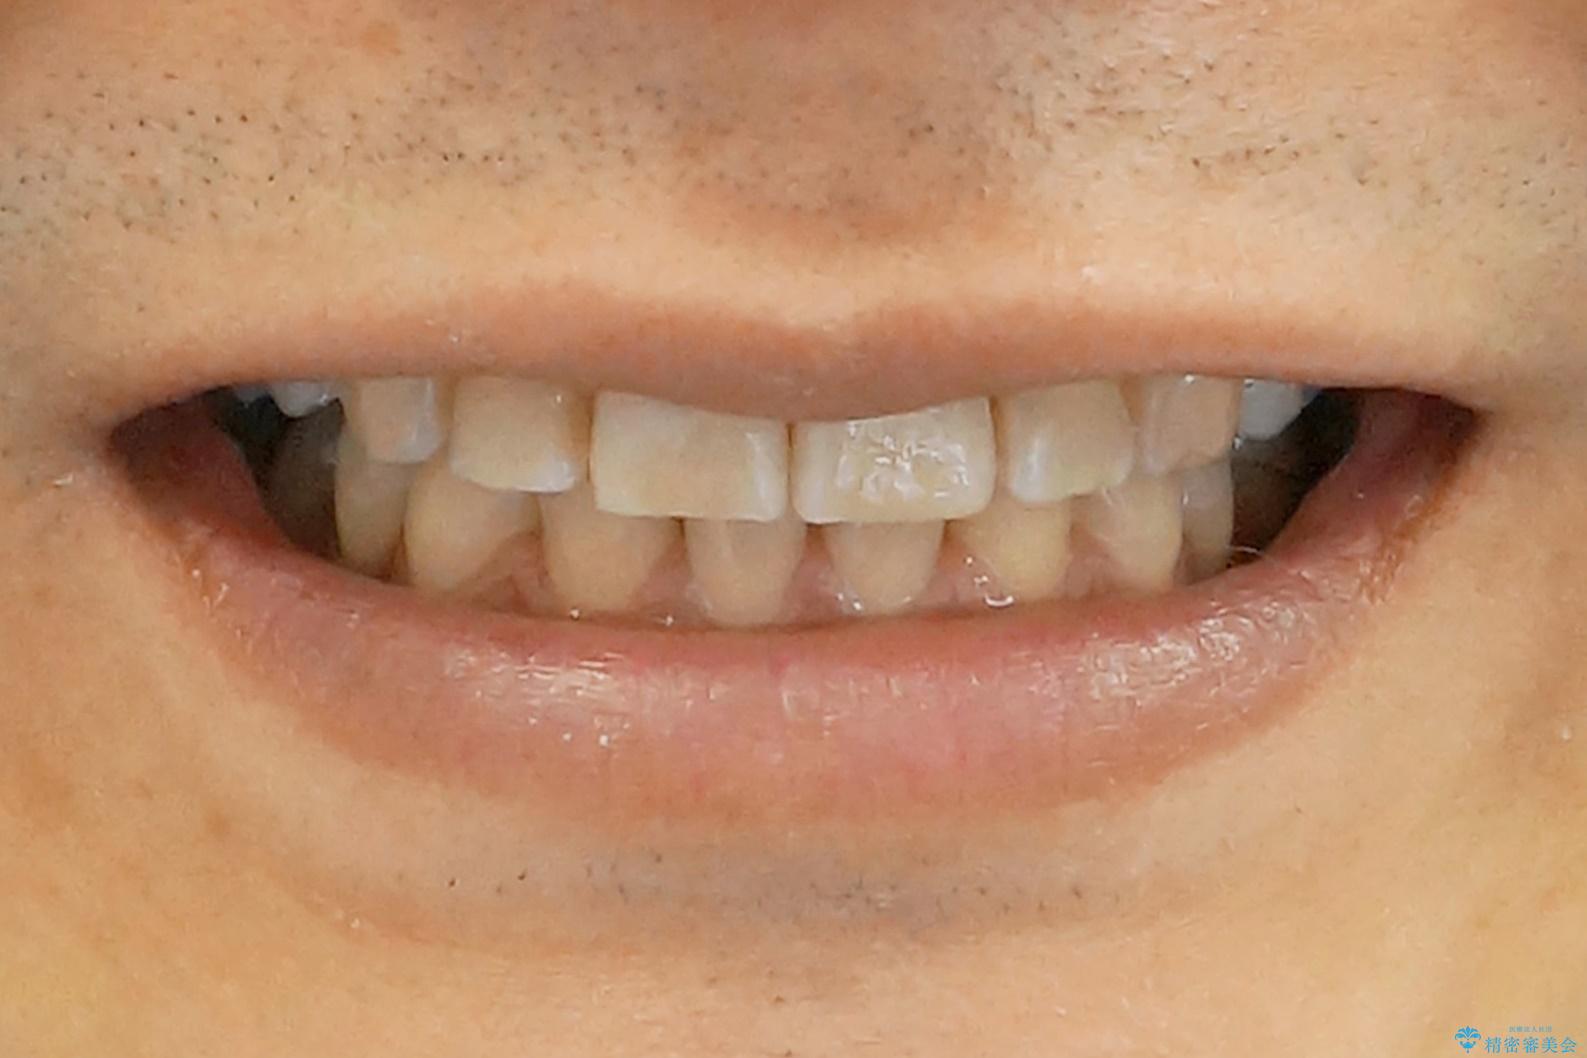

- 前歯だけ歯並びを治したいとのご希望で来院された患者様です。

数年前にワイヤー矯正を行ったものの、少し後戻りしてしまったそうです。

上の前歯が斜めに見えること、犬歯と小臼歯の間の隙間、上下顎前歯のがたつきを治すことをご希望されていました。

治療終了後、治療前後の写真をお見せすると「全然違いますね!」と喜んで下さいました。